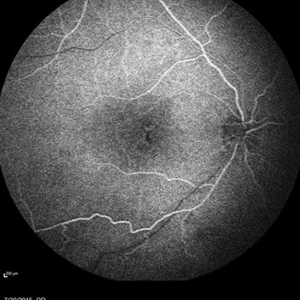

Retinal Dystrophy of 24-Year-Old Male Early FA OD

Fluorescein angiography of a 24-year-old male. Juvenile retinoschisis on OCT. FA shows outer retinal staining. Could be associated with Goldmann Farve Syndrome.

Condition/keywords: Goldmann-Favre Syndrome, juvenile retinoschisis, retinal dystrophy